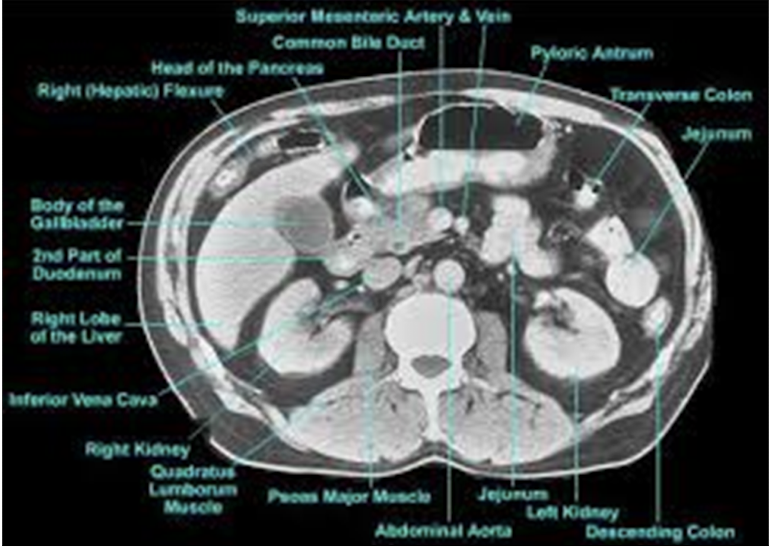

What is occurring in the CT scan?

Acute cholecystitis - enlarged gallbladder